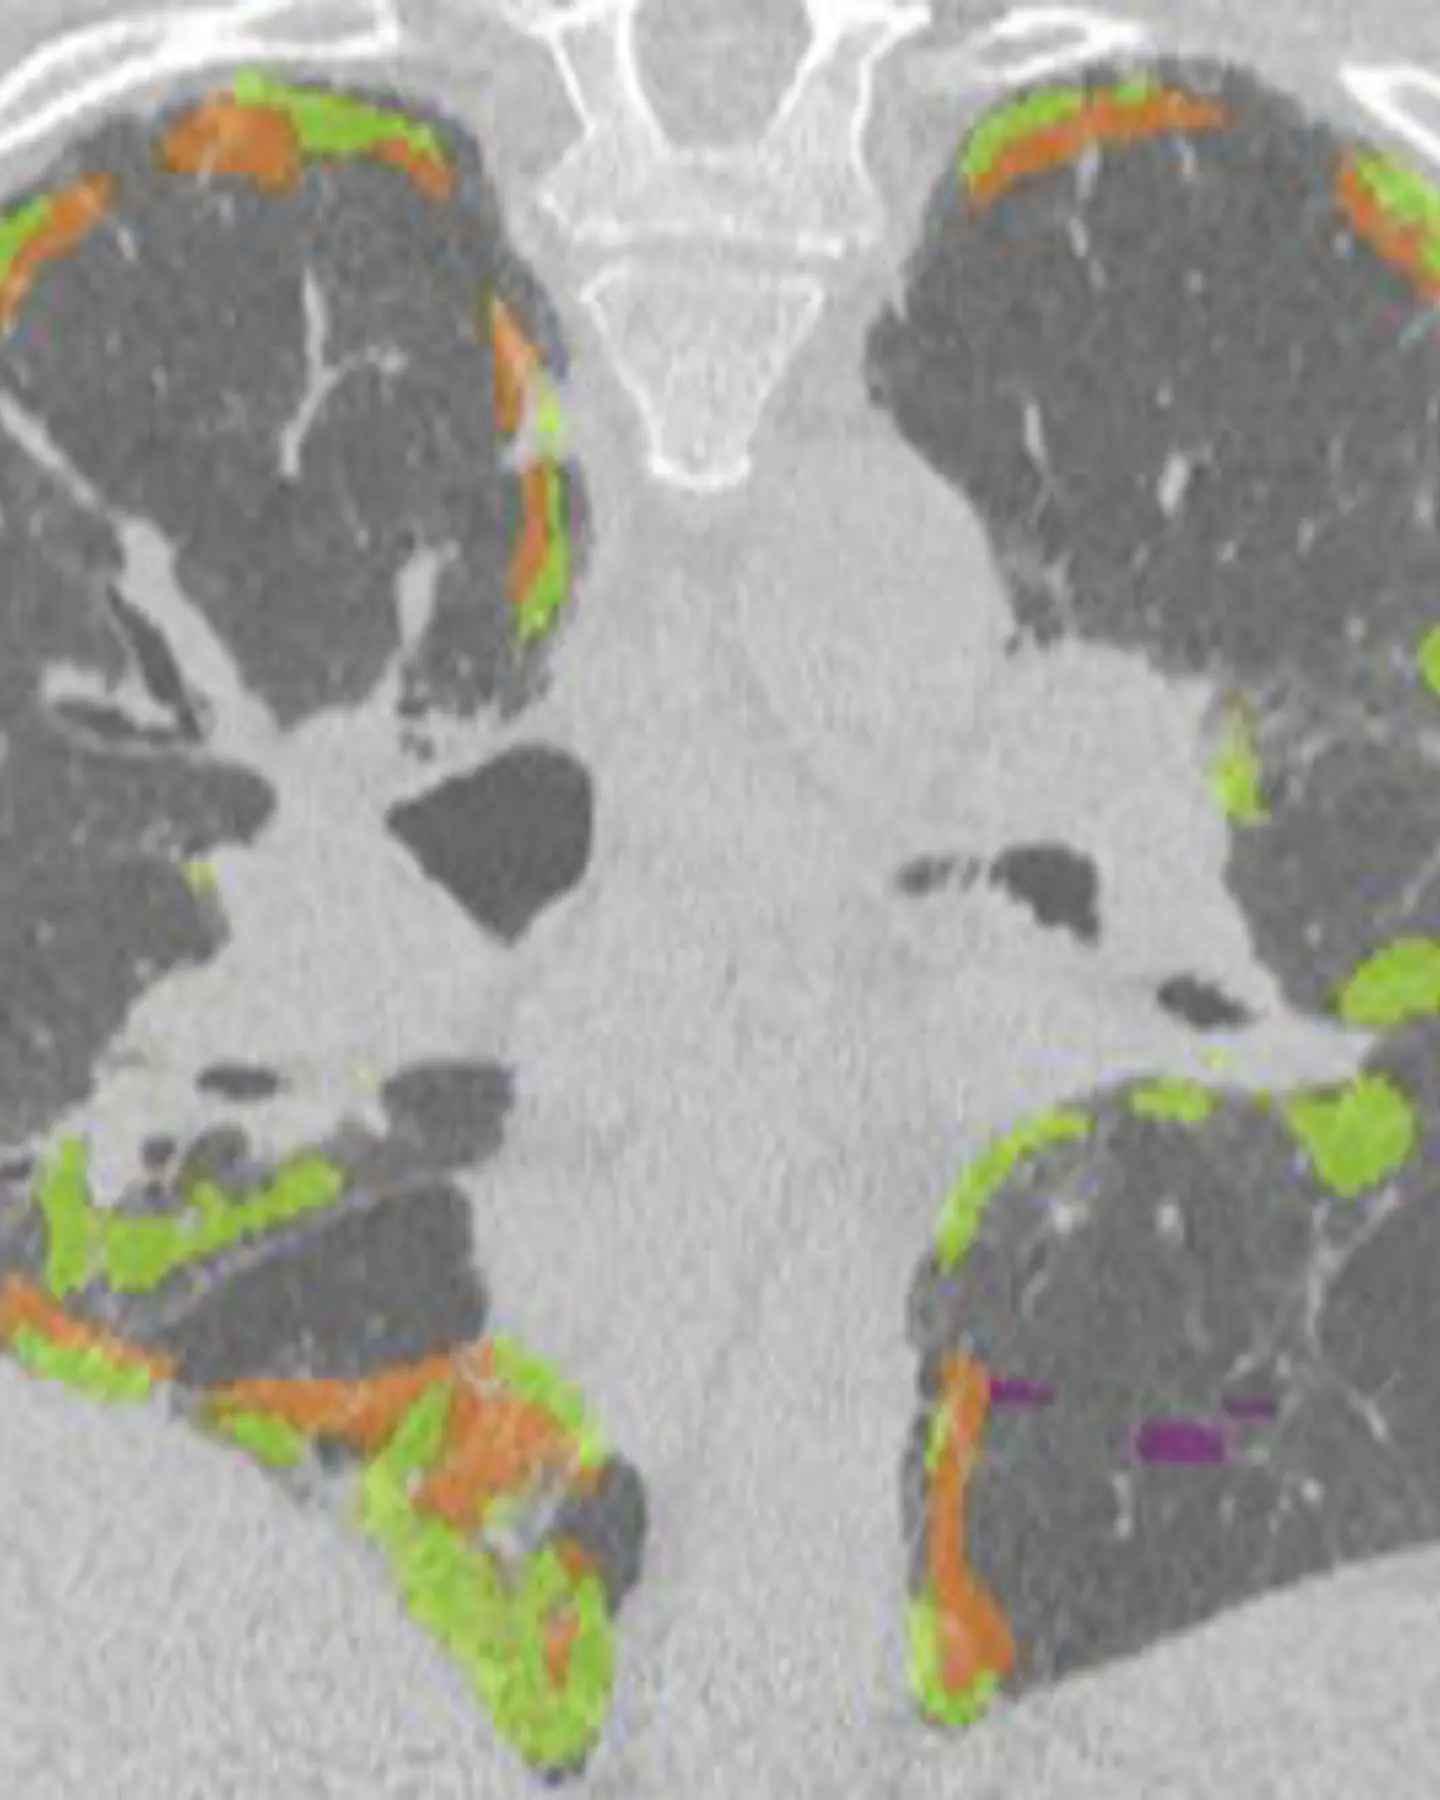

Our specialist lung assessment is used to diagnose a wide range of lung conditions utilising the expertise of specialist Cardiothoracic Radiologists and low-dose CT.

- Specialist report aided by Artificial Intelligence - for nodule detection and volumetry to guide management

Using the combined expertise of CT and specialist Cardiothoracic Radiologists, our specialist lung health assessment is used to assess and diagnose a wide variety of lung conditions. The assessment includes initial questions to evaluate your suitability for the assessment, lung cancer screening and a specialist report aided by Artificial Intelligence.